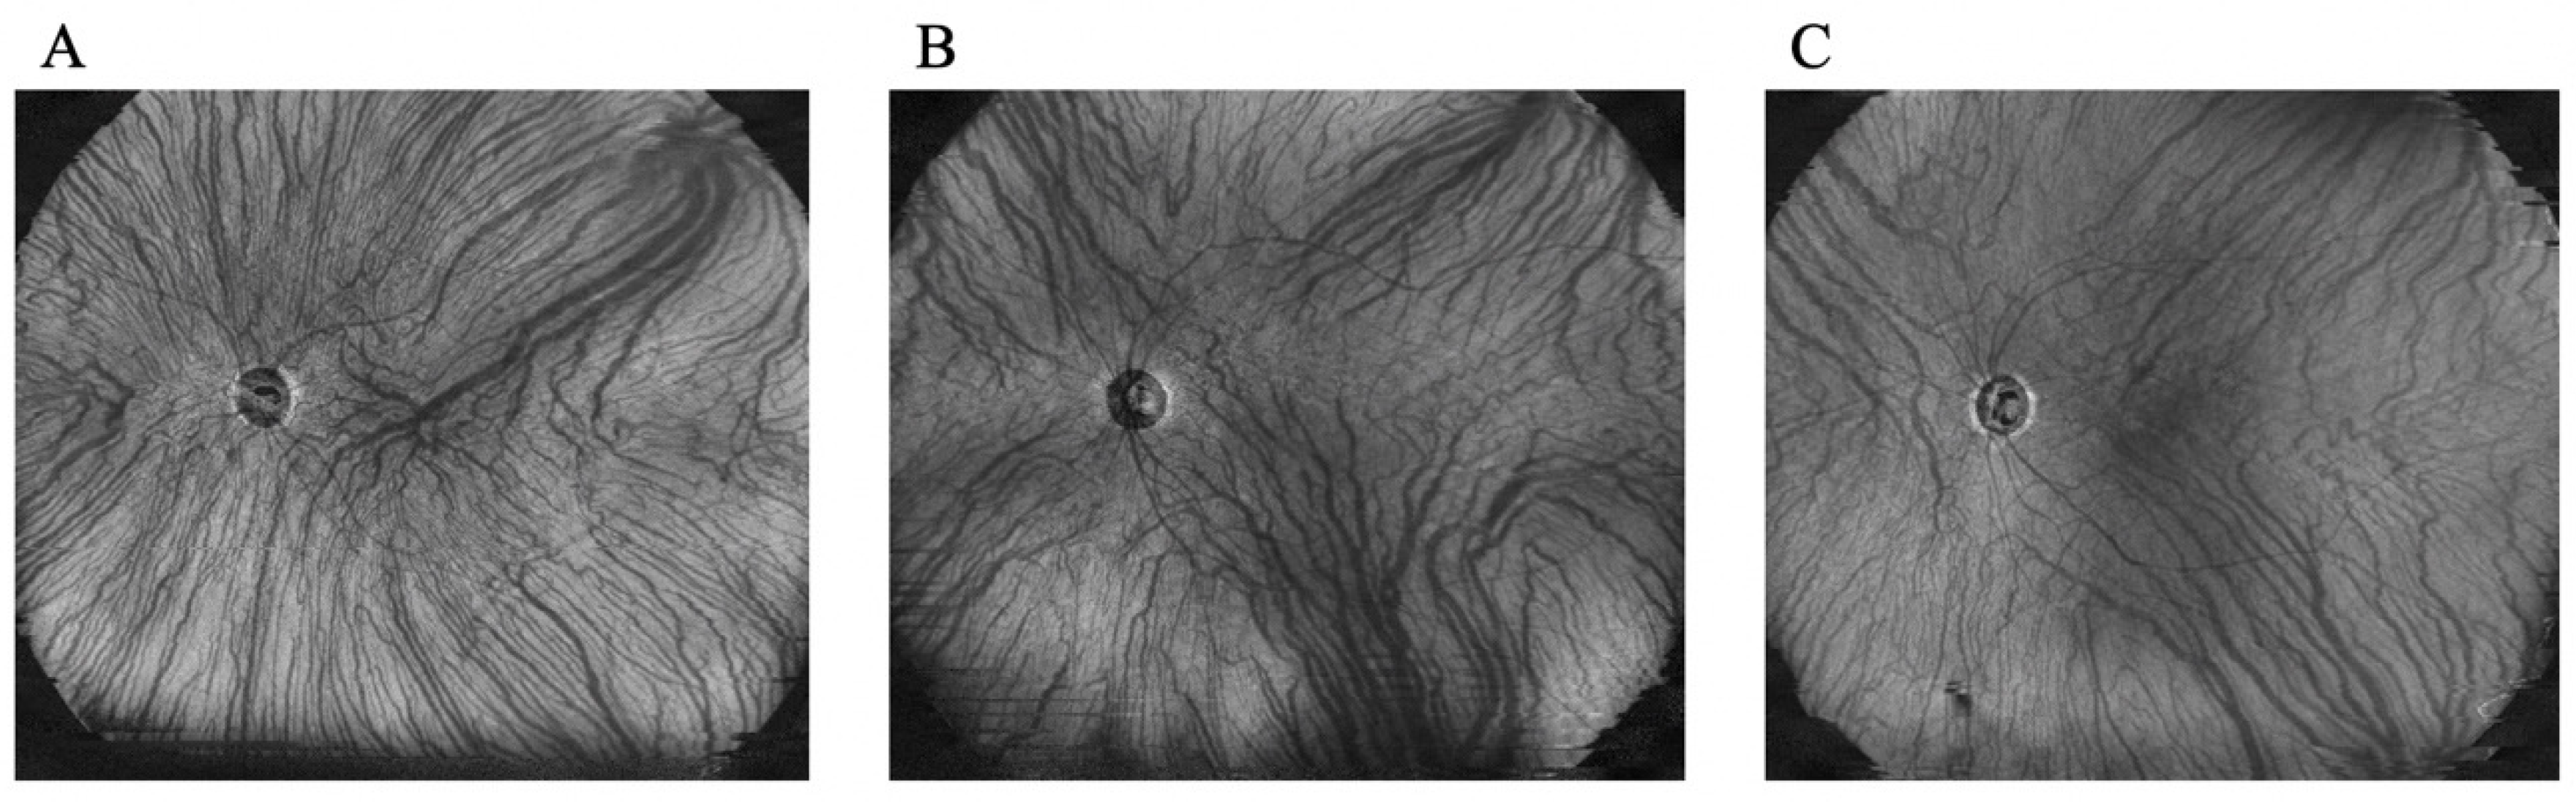

2.2. Evaluation of Choroidal Thickness via UWF Swept-Source OCT